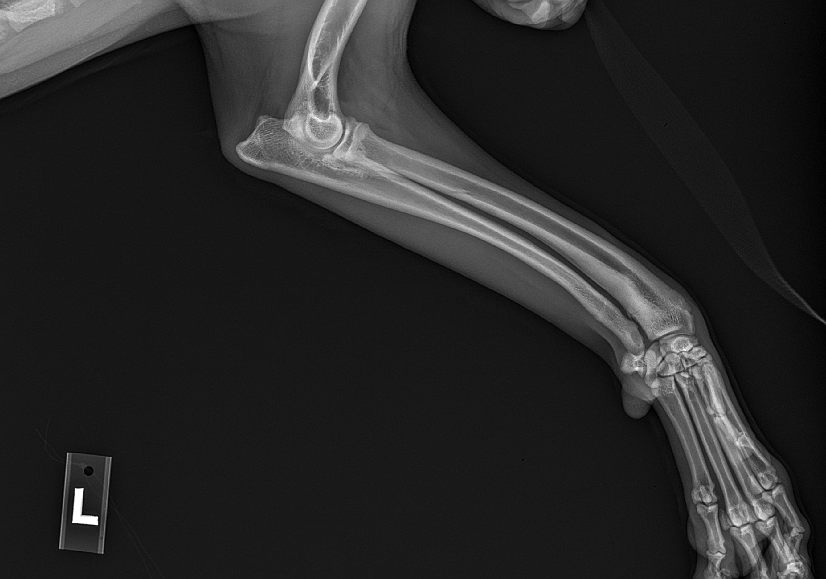

Rescued from the streets in Eastern Wa, Jake came to us with fractures from a broken back leg and musculoskeletal malformations in his front leg. Arthritis is already setting in. We are assuming he was hit by a car but never got taken to a vet for care. So his broken bones and legs healed as they were. Jake has learned how to get around using his back leg very carefully but the fact is he is in pain. His front leg is also of concern so it doesn’t get any worse.

Jake’s pain will need to be closely monitored with treatments and medication. Jake will be extremely limited in what he is able to do but he does a little running and wants to play with other dogs.

We would like to get Jake the continued medical help he needs. He is being seen by surgeon who is kindly offering a free evaluation and exam of Jake's X-rays to determine the best outcome for his care. Every animal we have in our car needs vet care, some more than others.